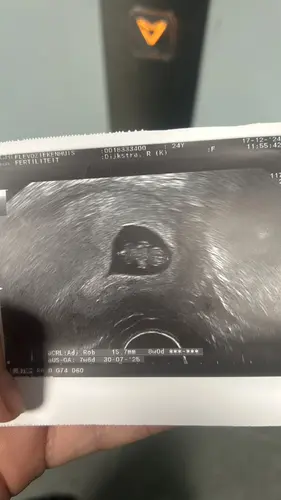

Heey, wat een ontzettend schattige echo! Ik zou persoonlijk nog even wachten met spulletjes kopen als dit je eerste kindje is :) wij hebben toen gewacht tot na de nipt en zelfs toen weinig gekocht, hoe hard t ook kriebelde. Pas toen we wisten dat het een meisje was, meer gaan kopen. Je hebt tijd zat.